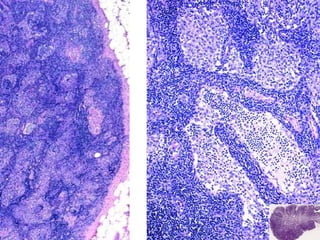

• #24 This marrow is virtually 100% cellularity!!! This is the HALLMARK of CML, and all the cells are still marrow cells although blasts are INCREASED, i.e., more than 1-2 %. The “spaces” are NOT fat, they are blood vessels. This marrow is virtually 100% cellularity!!! This is the HALLMARK of CML, and all the cells are still marrow cells although blasts are INCREASED, i.e., more than 1-2 %. The “spaces” are NOT fat, they are blood vessels.

• #25 This marrow is virtually 100% cellularity!!! This is the HALLMARK of CML, and all the cells are still marrow cells although blasts are INCREASED, i.e., more than 1-2 %. In this CML megakaryocytes are proliferating so what OTHER myeloproliferative disease could this be confused with? Ans: essential thrombocythemia (also called essential thrombocytosis)